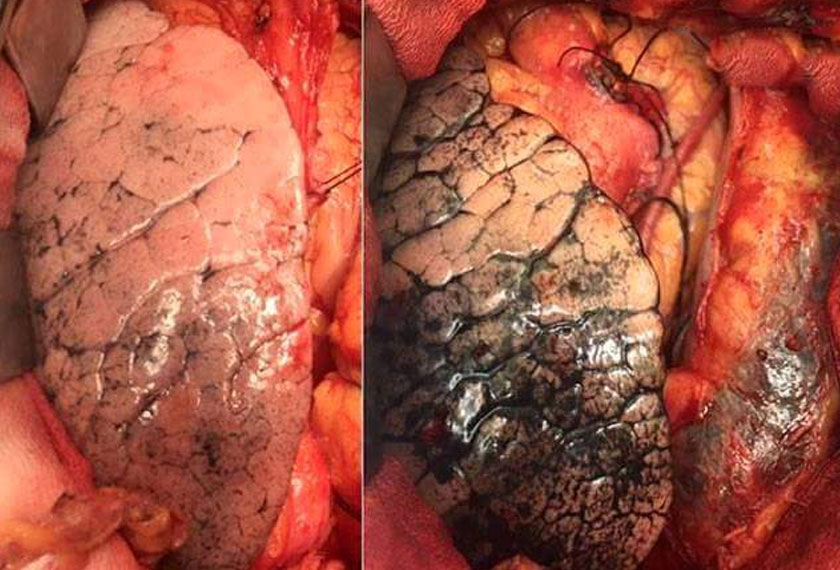

Tabiat ini boleh mendatangkan pelbagai jenis penyakit terutama penyakit kanser paru-paru, tekanan darah tinggi, strok, penyakit jantung dan mati pucuk.